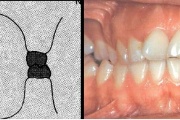

Vali sind huvitav pilt ja me näitame sellega seotud haigust ja sümptomeid